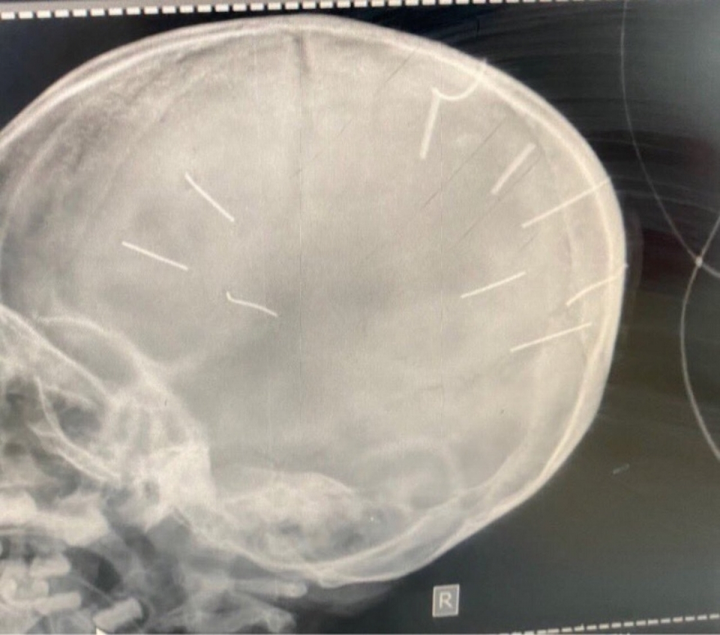

Hình ảnh X-quang sọ não bệnh nhân. (Ảnh: Bệnh viện cung cấp)

Trước đó, Bệnh viện Đa khoa huyện Thạch Thất tiếp nhận bé Đ.N.A. trong tình trạng nguy kịch, phim chụp X-quang cho thấy có đinh trong sọ, tiên lượng tử vong cao. Theo BS Vương Trung Kiên, Giám đốc Bệnh viện Đa khoa Thạch Thất, ngày 17/1, bé A. được mẹ đưa đến viện trong tình trạng hôn mê, co giật. Người mẹ này cho biết, do từ chiều gọi không thấy con tỉnh nên bà đưa A. đến viện.

Tại Bệnh viện Đa khoa Xanh Pôn, kết quả phim chụp cắt lớp cho thấy bệnh nhi Đ.N.A. có hình ảnh như bị đinh bắn vào hộp sọ.